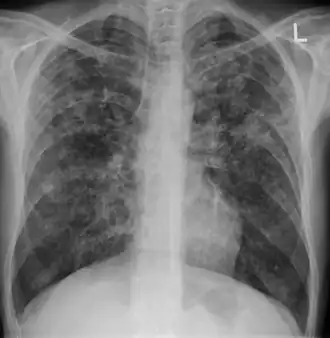

Chest x-ray showing patchy opacification on the upper right and mid-zone lung with fibrotic shadows, as well as bilateral hilar lymphadenopathy. -